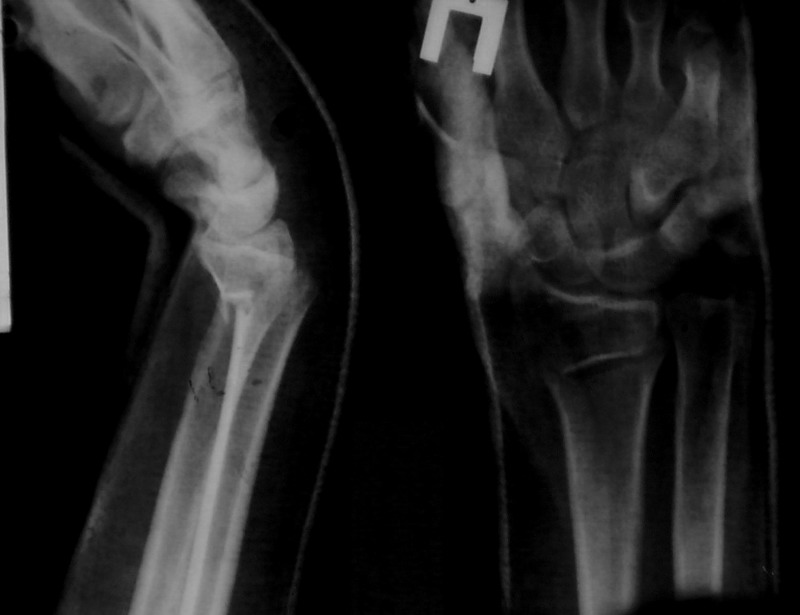

katsevman haim. tel a shomer, hand surgery - israel 12 Декабрь 2007, 20:48

v zavicimocti ot vosmoznoctei. perelom viglidit vne sustava - redukzia + 2-3 kirshnera. proverit posle etogo stabilnost distal radio ulnar joint, ecli ne stab fixatia kirshnerom obichno v polusupinacii.

А что беспокоит самого пациента? Если лечить рентгенограмму, то без ЧКДО не обойтись Прошло уже две недели. При отсутствии отека и неврологических расстройств - выведите кисть из положения гиперфлексии в функциональное в хорошо отмоделированной гипсовой повязке.

Гипс снял, временно одел ортез. Неврологических и других расстройств, отека - нет. Попробую произвести репозицию. Просто вывести кисть в функциональное положение без репозиции, думаю, ничего не даст. Угол

флексии суставной поверхности выше допустимого, и по оси недотянуто.

Уважаемый Сергей, такое стояние отломков неприемлемо. Целесообразна закрытая ручная репозиция под общим обезболиванием. при неудовлетворительном стоянии - операция открытая репозиция из волярного доступа, остеосинтез Т-образной пластиной. Либо если пациент "нормальный" сразу открытая репозиция, остеосинтез (достаточно просто, жесткая фикчация, ранняя функция)

Под проводниковой анестезией произвел аккуратную одномоментную репозицию, фиксацию гипсовой повязкой в положении умеренной экстензии. Думаю неплохо получилось. Мягкие ткани не вызывали опасений в плане Зудека.